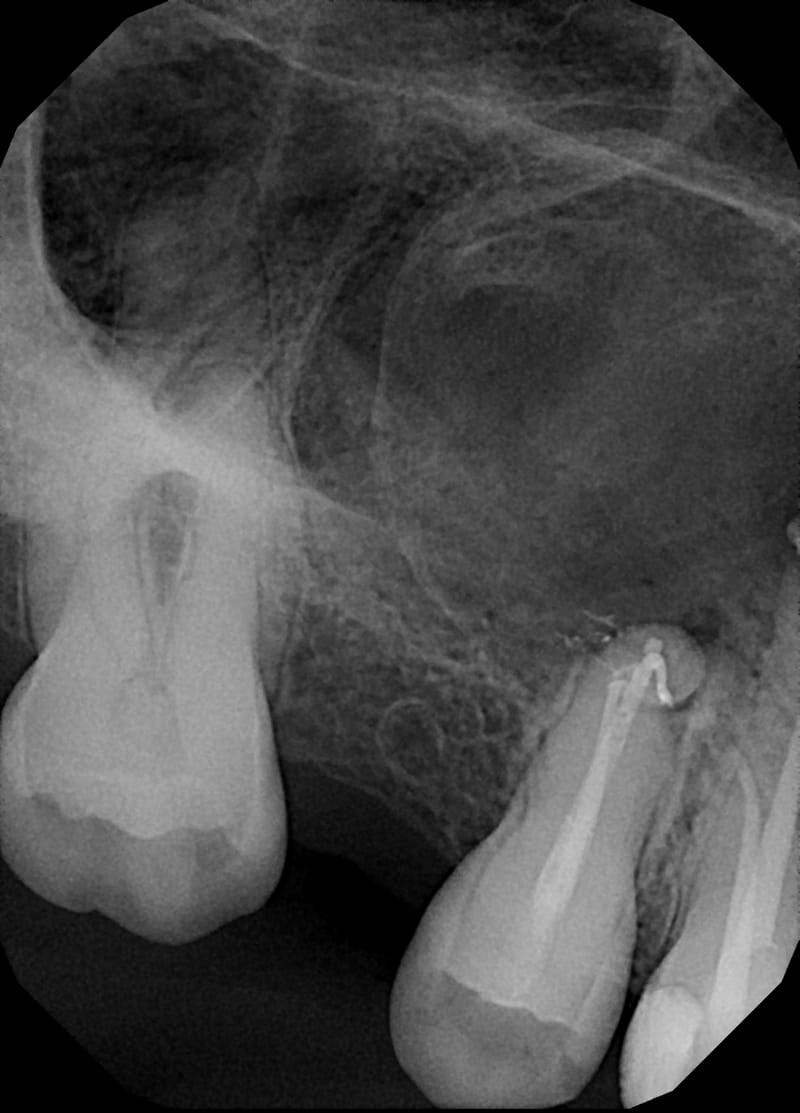

Leczenie pierwotne d.24